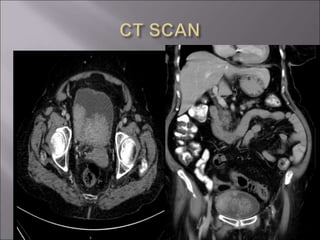

 CT SCAN

 ULTRASOUND  INTRAVENOUSUROGRAM  CT SCAN  CYSTOSCOPY  URINE CYTOLOGY  ROUTINE INVESTIGATIONS